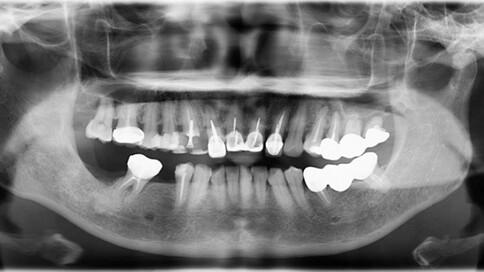

面對前牙(門牙)的缺損或美觀問題,我們通常會根據「修復範圍」與「牙齒健康狀況」,在全瓷冠與陶瓷貼片之間做選擇。

當您只有「單顆」門牙受損時,挑戰在於模仿隔壁那顆「天生的牙」。我們利用全瓷冠的高透光性創造視覺平衡,避免做出一顆看起來很新卻很突兀的假牙。